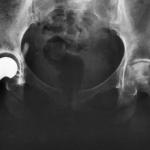

Metal-on-metal (MoM) hip implants have spawned massive recalls and thousands of lawsuits, some of which have been settled for billions of dollars. Now, Stryker’s V40 femoral heads have spurred an alert from the company warning against loss of mobility, pain, inflammation, and dislocation.

Now, Stryker’s V40 femoral heads—which are used in MoM hip replacements—appear hazardous enough to warrant an alert from the company warning against potential side effects, such as loss of mobility, pain, inflammation, and dislocation. In November 2018, Stryker reached a confidential settlement agreement that will resolve hundreds of V40 femoral head lawsuits.

In addition to the V40 femoral head, Stryker also manufactured the Rejuvenate and ABG II hip stems, both of which were recalled in 2012. These hip stems generated a flood of lawsuits filed by patients who suffered complications after their hip replacement surgeries. Many would need a second (or revision) hip surgery.